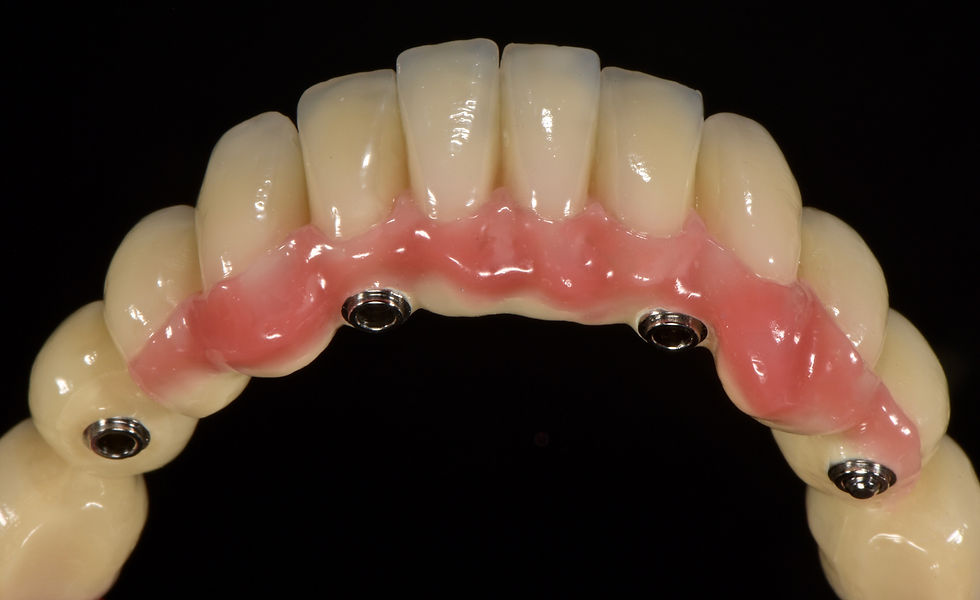

Occlusal view of the lower Toronto Bridge: screw passages are in favourable prosthetic positions

Details of the lower Toronto bridge

Relationship between the lower Toronto Bridge and the neck of Prama Long Neck implants